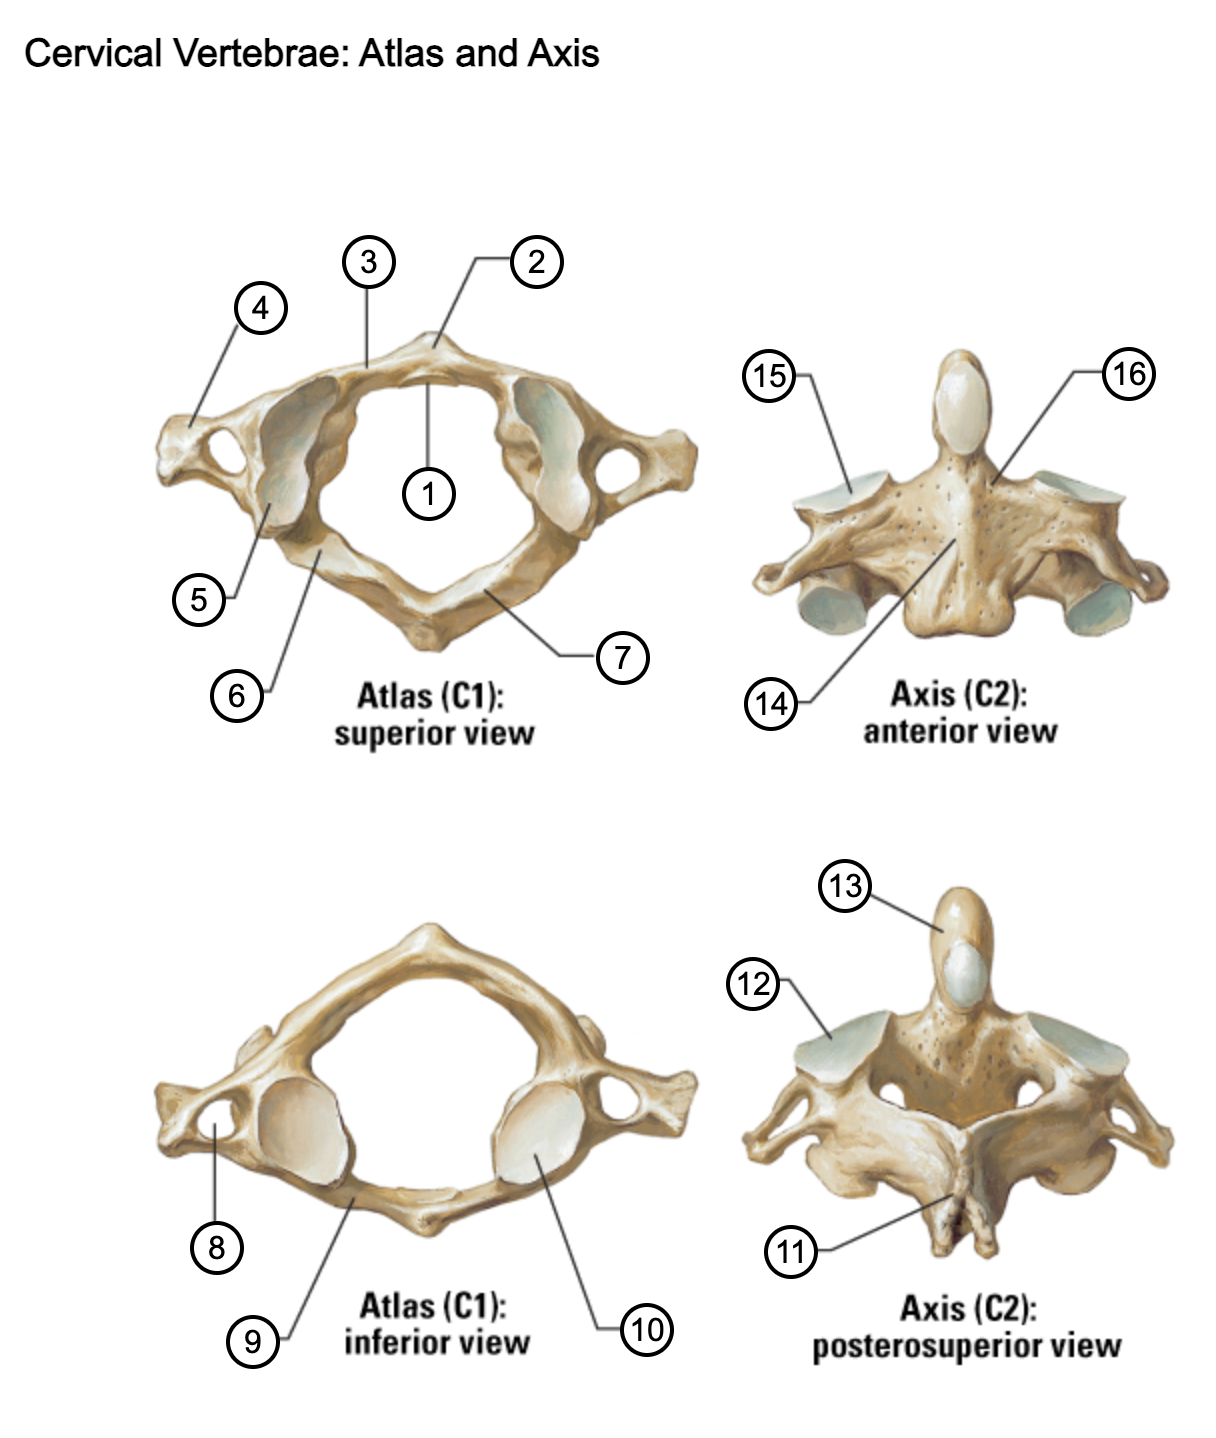

1

facet for dens

2

anterior tubercle

3

anterior arch

4

transverse process

5

superior articular surface of atlas

6

groove for vertebral artery

7

posterior arch

8

transverse foramen

9

anterior arch

10

inferior articular surface of atlas

11

spinous process

12

superior articular facet

13

dens of axis

14

body of axis

15

superior articular facet for atlas

16

pedicle of vertebral arch